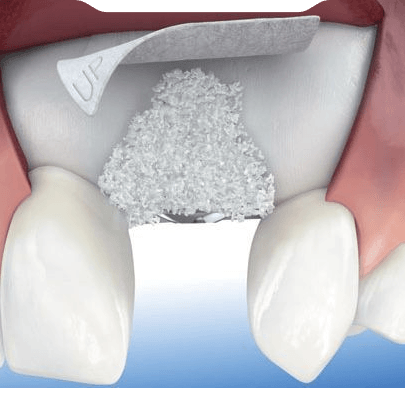

Anatomik olarak üst çenemizin üzerinde "Maksiller Sinüs" adı verilen hava boşlukları bulunur. Diş çekimi sonrası bu bölgedeki kemik inceldiğinde, implant yerleştirmek için yeterli mesafe kalmaz. Sinüs Lifting, bu boşluğun tabanındaki membranın cerrahi olarak yukarı kaldırılması ve altına kemik grefti (kemik tozu) yerleştirilmesi işlemidir.

- Açık Sinüs Lifting (Lateral Window): Kemik kaybının çok ileri seviyede olduğu durumlarda tercih edilir. Sinüs bölgesine yandan küçük bir pencere açılarak kemik tozu ilavesi yapılır. İyileşme süreci sonrası (4-6 ay) implant aşamasına geçilir.